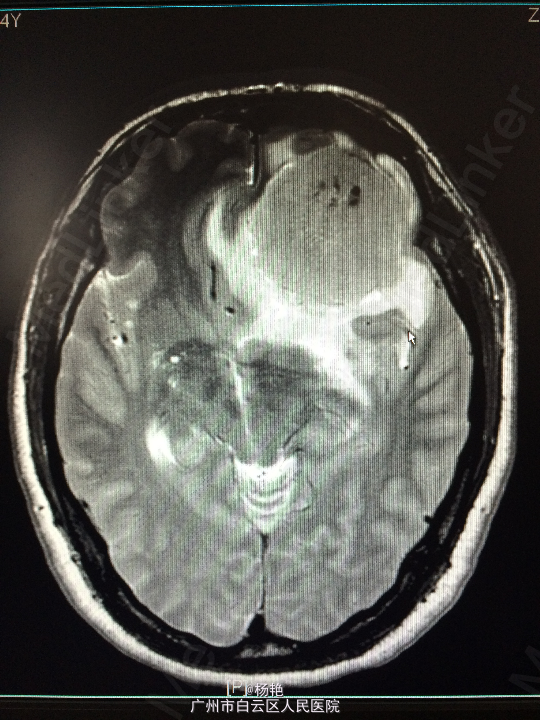

主诉:反复头痛2年加重1周 病史:患者诉两年前无明显诱因反复出现头晕头痛不适,近一周来症状加重,无恶心呕吐、无行走不稳、肢体乏力、意识障碍等。遂至当地医院诊治,行头颅CT、MR检查均提示颅内占位,良性可能性大,考虑脑膜瘤。今患者为求进一步治疗而入我院。

查体:神经系统查体未见明显异常 辅助检查:头颅MR提示:左侧额叶区域较大类圆形肿物,多考虑脑膜瘤可能;大脑前动脉及中动脉受压,中线偏移。

诊断:左额叶脑膜瘤 处理:在静脉全麻下行左侧额底脑膜瘤切除术,术后病理提示:脑膜瘤

术后患者左侧视力稍模糊,无其他不适,出院 讨论:脑膜瘤属于良性肿瘤,生长慢,病程长。因肿瘤呈膨胀性生长,病人往往以头疼和癫痫为首发症状。根据肿瘤位置不同,还可以出现视力、视野、嗅觉或听觉障碍及肢体运动障碍等。在老年人,尤以癫痫发作为首发症状多见。颅压增高症状多不明显,尤其在高龄病人。在CT检查日益普及的情况下,许多患者仅有轻微头痛,甚至经CT扫描偶然发现为脑膜瘤。因肿瘤生长缓慢,所以肿瘤往往长的很大,而临床症状还不严重。临近颅骨的脑膜瘤常可造成骨质的变化。手术切除脑膜瘤是最有效的治疗手段。随着显微手术技术的发展,脑膜瘤的手术效果不断提高,使大多数病人得以治愈。